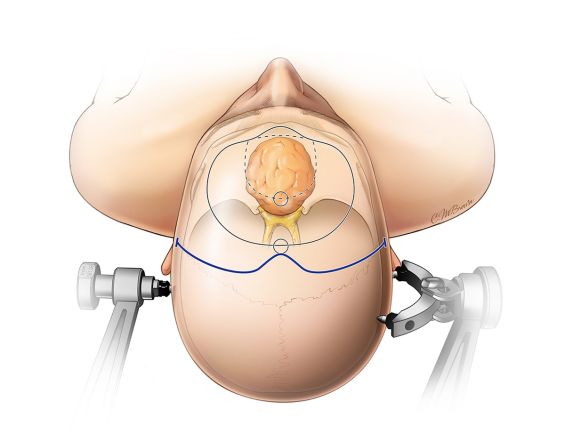

患者头部旋转45°,以保证在打开硬膜后可以处理对侧鸡冠。对于巨大的肿瘤,骨窗应向内侧适当扩大,但仍应保持在额窦的外侧。暴露角度应与眶顶平行,以确保可以到达肿瘤的根部。但没有必要进行眶颧切除。

图7. 肿瘤在体表、体内定位及标志。头部旋转45°。非优势半球一侧作为该中线肿瘤入路的首选。